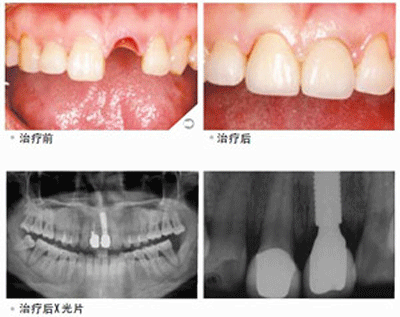

种植牙术推荐:即刻种植

福州爱尚贝臣口腔门诊部有限公司率先引进微创即刻种植术,国内医生级医生进行种植牙手术,利用手术方式来完成种植牙过程。与传统的种植牙相比,具有以下优势:

1.创伤小,无痛苦。仅有几毫米的微小切口,将人工牙根“种”入口腔内,摆脱了传统种植牙缝合、拆线等步骤,创伤小,术后即可进食,几乎无痛苦。

2.时间短,方便快捷。一般情况下,种植体植入手术只需要数十分钟即可以完成,大幅缩短拔牙后的等待时间,快速修复牙齿。

3.效果好,无副作用。由于选用的是与人体相容性较好的材料,种植牙对人体不会产生任何不良的副作用,对牙齿没有任何损伤,安全可靠。

4.稳固性好,舒适度强。人工牙根与牙槽骨紧密结合,就像真牙似的扎根在口腔里,因此具有很强的稳定性,而且无需卡环或牙套,所以口腔内没有异物感,非常舒适方便。